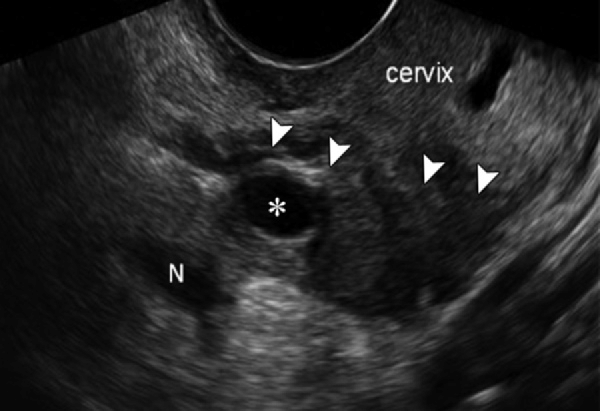

Ультразвуковое исследование не является базовым исследованием для диагностики ретроцервикального эндометриоза, потому что ограничено в оценке глубины инфильтрации, различии активных и фиброзных очагов и визуализации слабовыраженных перитонеальных включений при невыраженных анатомических смещениях. Ретроцервикальный эндометриоз представляет собой форму наружного эндометриоза с поражением позадишеечного пространства, сопровождающуюся болевым синдромом, диспареунией и нарушениями функций тазовых органов. Для диагностики назначаются магнитно-резонансная томография и лапароскопия. Косвенно УЗИ выявляет следующие анатомические признаки:

В серошкальном режиме визуализируется гипоэхогенный участок неправильной формы в проекции заднего свода влагалища и позадишеечного пространства, структура соответствует эндометриоидной инфильтрации с нечёткими границами, стенка заднего свода выглядит утолщённой и ригидной, матка смещается кпереди и может быть фиксирована, а прямая кишка приближается к задней поверхности шейки с утратой нормального межорганного скольжения.

В режиме сканирования мягких тканей определяется снижение эхогенности парацервикальной клетчатки и увеличение толщины крестцово-маточных связок, структура соответствует воспалительной инфильтрации и рубцовой трансформации.

В допплеровском режиме выявляется минимальный или отсутствующий кровоток в пределах инфильтрата, что подтверждает преобладание фиброзного компонента при хроническом течении.